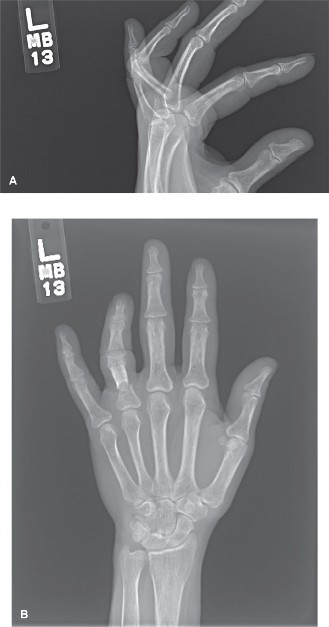

CASE 25 A 42-year-old man presents to the hospital with pain and swelling of th…